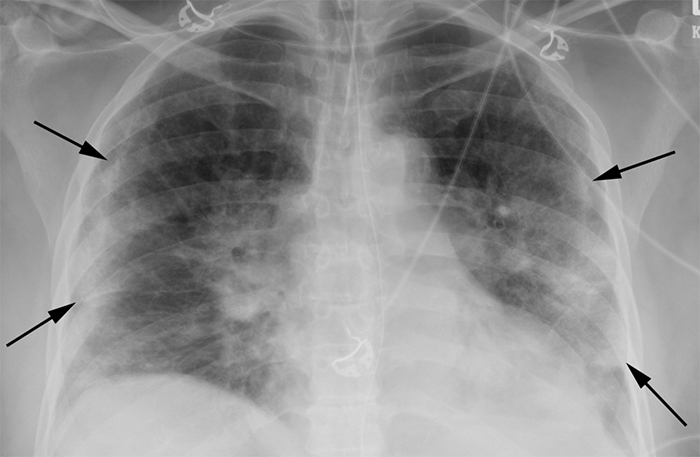

Diagnostic Impact Of Bedside Chest X Ray Features Of 2019 Novel Coronavirus In The Routine Admission At The Emergency Department Case Series From Lombardy Region European Journal Of Radiology